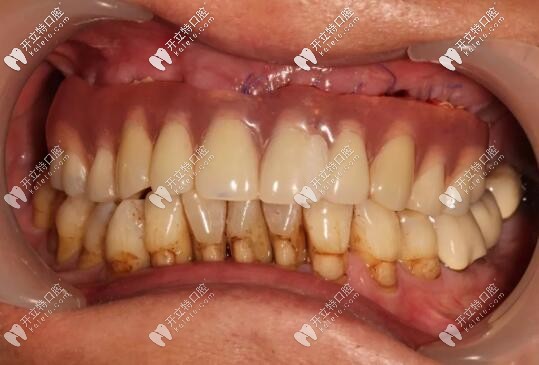

主訴:上頜活動(dòng)義齒不適,重新修復(fù)。

修復(fù)前

病史上頜于10年前因牙周病導(dǎo)致的牙齒缺失,曾做過可摘戴活動(dòng)義齒修復(fù)。